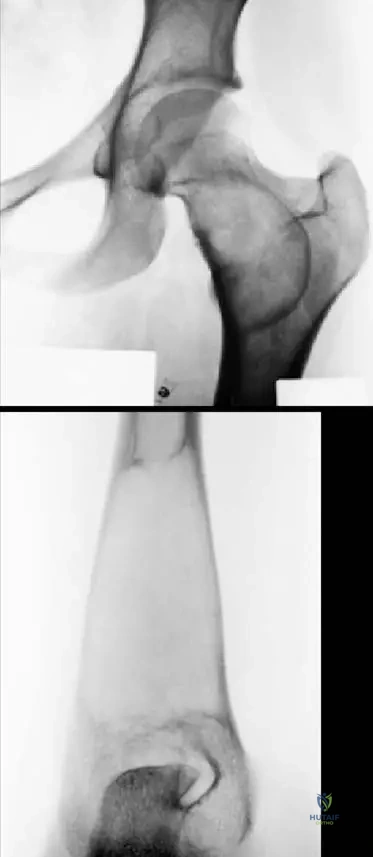

A 16-year-old female with polyostotic fibrous dysplasia affecting her femur and pelvic bone undergoes an MRI for further evaluation of a painful lesion. What general appearance would be expected on MRI, consistent with the radiographic findings?

View Answer & Explanation

Correct Answer: C

Rationale: The text states that "The lesions are usually benign-appearing, presenting a bubbly lytic or mixed lytic and sclerotic lesions with a narrow zone of transition and a sclerotic margin as seen in this patient with polyostotic disease affecting both the femur and pelvic bone as presented on the radiograph (a) and MR imaging (b)." This description directly applies to the expected appearance on MRI as well, reflecting the mixed fibrous and osseous components. Aggressive periosteal reaction would suggest a malignant process.

A 57-year-old male presents with a 2-month history of progressive left arm pain and weakness. Radiographs reveal a lytic destruction of the shaft of the left humerus. A subsequent bone scan shows increased uptake in the affected area, and a CT abdomen identifies a primary site in the kidney. What is the expected radiographic appearance of metastatic bone disease?

Correct Answer: D

Rationale: The clinical text explicitly states, "The radiographic appearance of metastases is highly variable. The appearance will vary from radiolucent to radiodense; some tumors have a mixed character." This directly addresses the variability in radiographic presentation. The image (Fig. 8.123a) shows a lytic lesion, but the text emphasizes the broad spectrum. Options A, B, and C are incorrect because they suggest a single, consistent appearance.